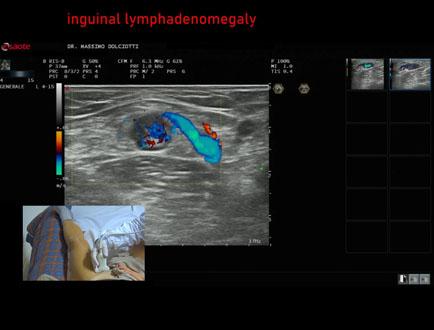

Data inserimento: 20/03/2025

Ecografia del: 10/03/2025

Strumento: Esaote MyLab Eight

Sonda: Lineare Multifrequenza 4-15 MHz

Età Paziente: F 50 anni

Motivazione dell'esame: tumefazione dolente all'inguine sinistro.

Commento all'esame: le immagini ed il video documentano la linfoadenomegalia inguinale sinistra, con spiccato incremento della vascolarizzazione, da ricondurre a linfonodo reattivo per ascesso a gluteo sinistro.

Conclusioni: linfoadenomegalia inguinale reattiva sinistra (left reactive inguinal lymphadenomegaly).

Presentazione: Dr. Massimo Dolciotti - Ancona

Elaborazione digitale: Andrea Dini - Ancona